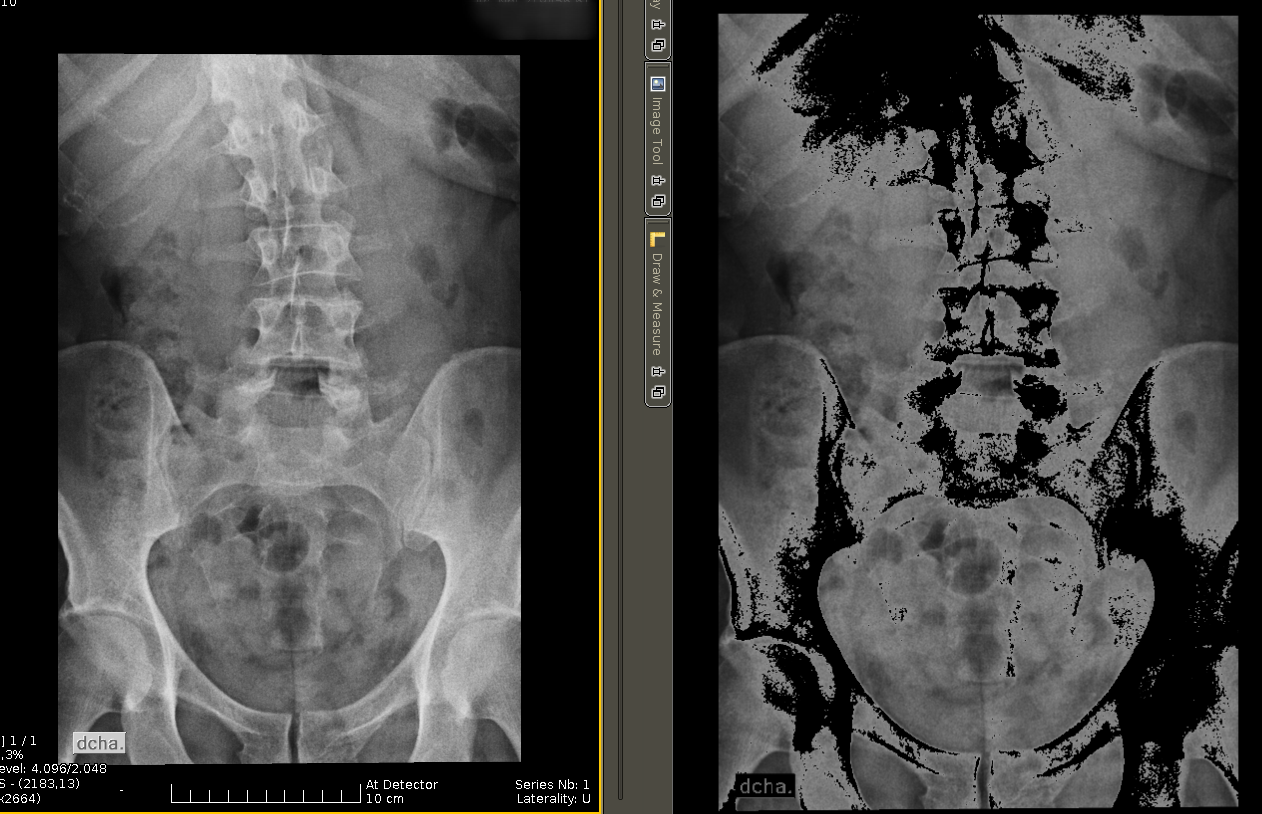

Wrongly displayed image

Hi, I have this image that is correctly displayed in Weasis (left) but wrong in Cornerstone (right). The image is loaded using CornerstoneCore 2.3.0 and CornerstoneWADOImageLoader 3.3.1, originally encoded as Jpeg Lossless.

The image is part of a study that contains other images without this issue, can anyone help me with this?.

Hello, I also encountered this problem. For me it was due to a bad minPixelValue or maxPixelValue in the loadedImage which was set either too high or too low creating those black sports (or white spot) where the pixel Value where below the minPixelValue.